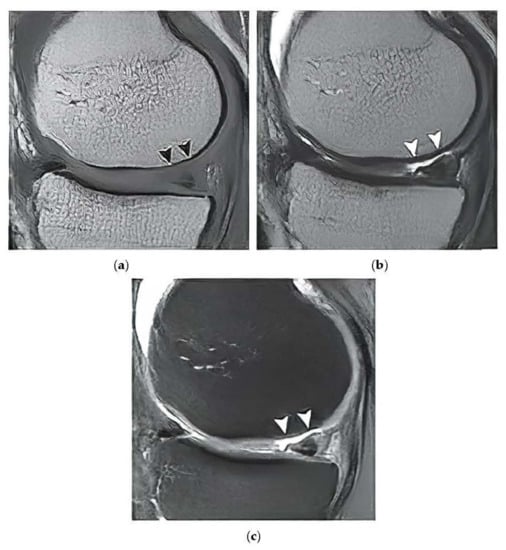

Based on the reported analysis of the segmentation performance, mostly the combination of fuzzy thresholding with the ABC evolutionary algorithms appeared as the best segmentation strategy, judging by reported objectivization parameters and mainly provided statistical tests of significance. In this subsection, we would like to provide the last analysis of selected features extraction of articular cartilage from MR images based on the fuzzy thresholding with the ABC algorithm. The aim of this analysis is firstly computing a multiregional segmentation model, allowing for a decomposition of the MR image into a finite number (in this case five) segmentation regions. Consequently, a region, representing the articular cartilage, is selected (Figure 20) as the region of interest, while the rest of the segmentation regions are suppressed from the segmentation model (Figure 20). By this selection scheme, we obtain a binary segmentation model, exclusively classifying the articular cartilage from the rest of the tissues in the MR images. Figure 20 also presents a multiregional segmentation of a part of articular cartilage (femoral cartilage) affected by osteoarthritis of I. grade, which is notable by two segmented lobes of the articular cartilage, and between them is a gap, where the cartilage is missing. To objectize the quality of the articular cartilage extraction and the preciseness of the reported features, we extracted the same features for the gold standard manual segmentation of articular cartilage. Consequently, the feature differences are compared to quantify the segmentation effectivity of articular cartilage detection. Note that we used the following settings for the ABC algorithm: 100 iterations and population size 50. The following cartilage features are considered for evaluation:

Figure 20. Example of segmentation results for articular cartilage and its features extraction based on fuzzy thresholding with ABC optimization: (a) gold standards by manual annotation, (b) binary segmentation, (c) native MR image with area of interest indicated by the green square (top) and multiregional segmentation with 4 regions (bottom), where yellow contours reflect two lobes of articular cartilage from region of interest, and (d) binary extraction of articular cartilage fused with the gold standard (red contour).

Based on the segmentation form as binary images, representing extracted articular cartilage and its respective features, we compute descriptive statistics, pointing out on individual distribution’s error functions, which show percentual differences of individual features, and a distribution of values for the individual parameters of segmentation performance (SSIM and index of correlation). Here, the evaluation parameters were computed between the gold standard binary image and the results of the fuzzy thresholding with the ABC algorithm. Figure 21 provides a graphical representation of the distributions of differences for cartilage features and the distribution of values for performance parameters for fuzzy soft thresholding with ABC optimization.

Based on the results of the quantitative analysis of difference function for the extracted features, we did not achieve significant differences between the gold standard images and fuzzy soft thresholding with the ABC algorithm. Mostly the distributions of difference function are kept under 6% of difference. Based on this analysis, we provide the descriptive characteristics (Table 13), which reports the median and standard deviation for each parameter. Based on these results, the best result in median difference is achieved for the feature of skeleton length (2.42%); contrarily, the worst median difference is achieved for the area (4.12%). From the view of measuring variability (standard deviation) of the difference function, the lowest difference is achieved for the skeleton (1.38%) in the contrast with the parameter area, where the difference was the worst (2.44%). The second studied aspect is the performance parameters: the index of correlation and the SSIM. Here, we achieved a higher median for correlation (0.94), where the median for the SSIM was 0.89. Furthermore, from the view of standard deviation, representing the concentration of values is better than the index of correlation (0.017), while in SSIM we achieved 0.028.